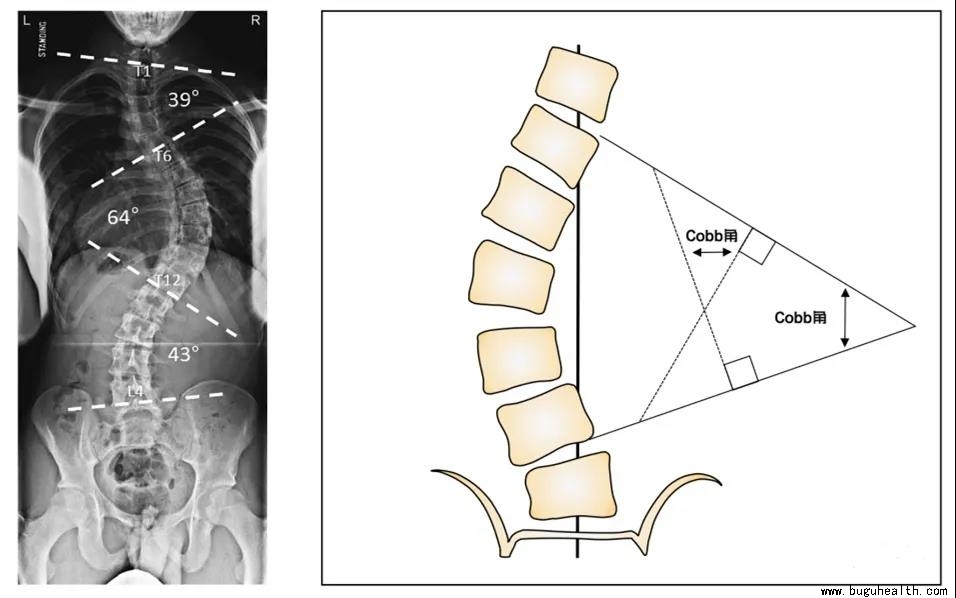

脊柱侧弯,顾名思义就是脊柱的侧向弯曲,指脊柱偏离人体的中轴线,出现了侧方的弯曲伴有椎体的旋转的三维脊柱畸形。国际脊柱侧弯研究学会(Scoliosis  Research  Society,SRS)将脊柱侧弯定义为——站立位脊柱正位X片Cobb角测量大于10°。

Cobb角,侧弯上下最倾斜的两个椎体,也就是端椎,沿上端椎上缘和下端椎下缘分别画两条射线,再做两条线的垂线的相交形成的角。

如何通过X片判断椎体旋转程度?

孩子脊柱侧弯后,从体表上观察,首先是背部高低不平,这就是椎体旋转造成的,俗称“剃刀背”。椎体旋转越厉害,剃刀背就越明显。国际上通用方法是通过椎弓根投影到片子上的类似两个小眼睛的部分来判断。

0°——正常,椎体无旋转。

1°——双椎弓根影向凹侧移位,但凹的部分不消失。

2° ——凸侧弓根影向中线移位,凹侧的部分完全消失。

3°——凸侧椎弓根影移到中线,凹侧的完全消失。

4”—凸侧椎弓根影越过中线。